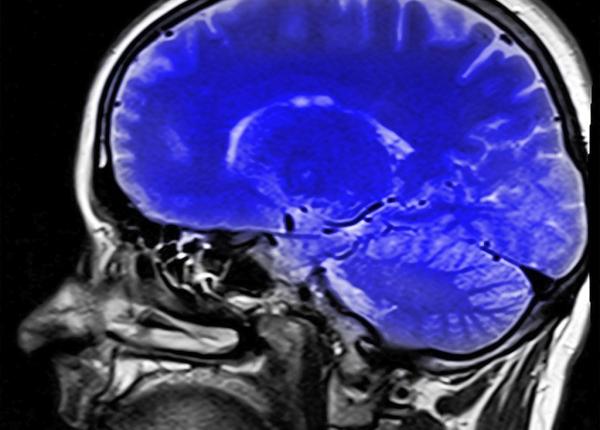

Creier: s-a descoperit zona care controlează planificarea și controlul

Cercetătorii au găsit acea zonă din creier care se ocupă de funcțiile executive precum rezolvarea problemelor, planificarea propriilor acțiuni, controlul emoțiilor.